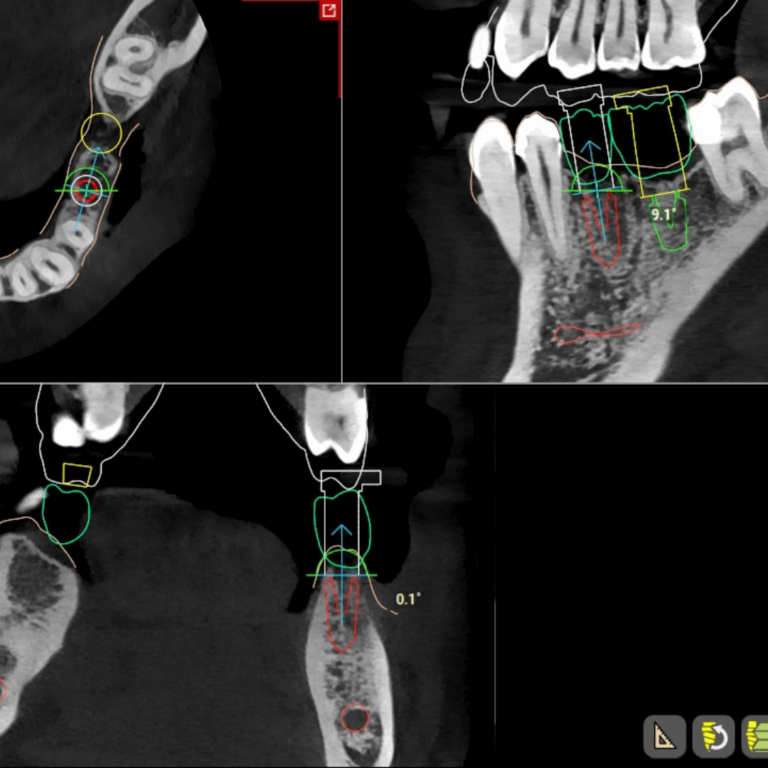

- Surgical Implant Guides